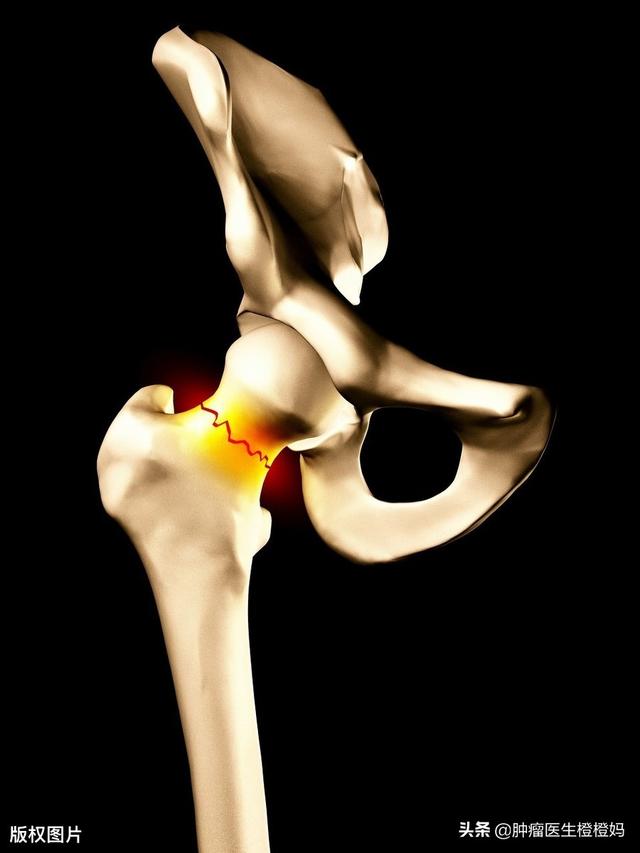

- 病的骨折:なぜ病的骨折と呼ばれるのか?これは骨に病変がある、つまり骨転移があって骨折するのであって、おなじみの「腕が折れた、足が折れた」というような骨折とは違うからだ。骨転移を起こすと、骨の安定性や硬さが以前ほど良くなくなるため、誤って転んで骨折し、病院で検査を受けて初めて骨転移が見つかるケースが多い。このタイプの骨折は通常、大腿骨頸部や大腿骨などの荷重の大きい部位、つまり太ももの骨に起こりやすい。

骨転移が骨、一般的には肋骨に発生した場合にも病的骨折が起こることがありますが、これは転移が骨の正常な構造を破壊するため、骨が弱くなり、外力が加わったときに骨折しやすくなるためです。骨転移の中には、骨の周囲に軟部組織の腫瘤として現れるものもありますが、体表には現れないため、発見するのは容易ではありません。病的骨折(下の矢印)